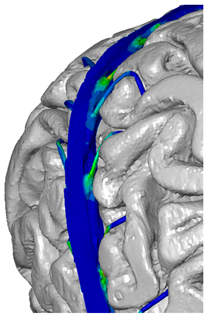

| Cerebrospinal fluid (CSF) | DYNAmore GmbH 2018; Gomez-Gesteira et al., 2012 [32,36] | 1 × 10−9 | – | viscosity coefficient 7 × 10−10 | SPH 191,406 | ![]() |